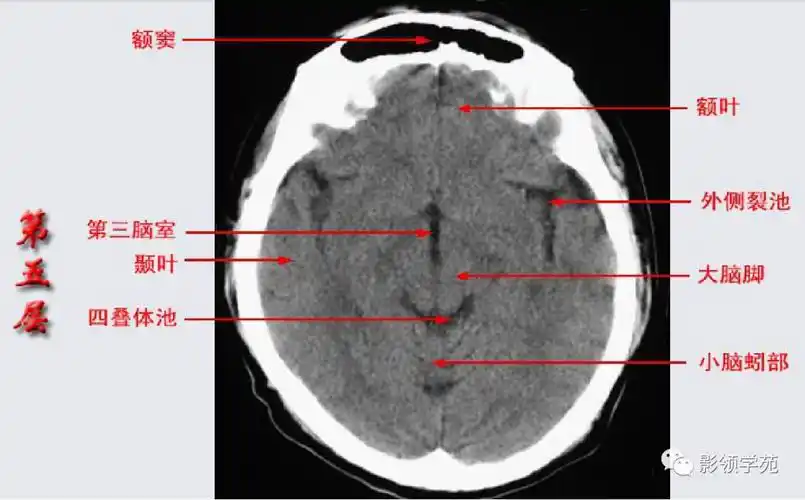

头颅ct解剖与常见出血梗死判读

解剖颅脑ct断层中英文对照干货满满